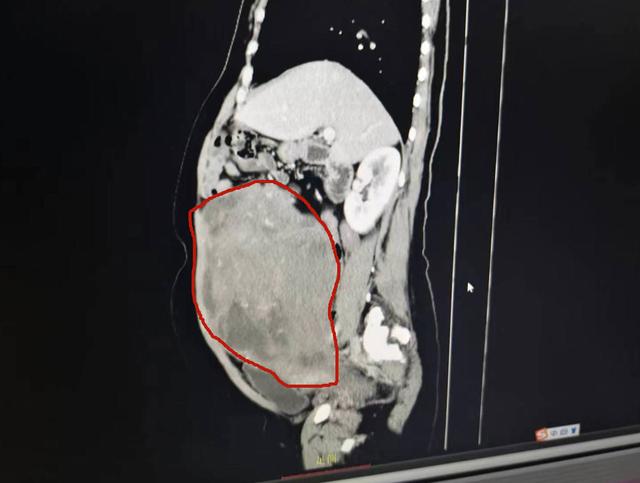

子宫肌瘤大如篮球,常州妇保院专家轻松"拆弹"

复查妇科b超提示,卢女士腹中罕见地藏了十多个子宫肌瘤,整体大小堪比